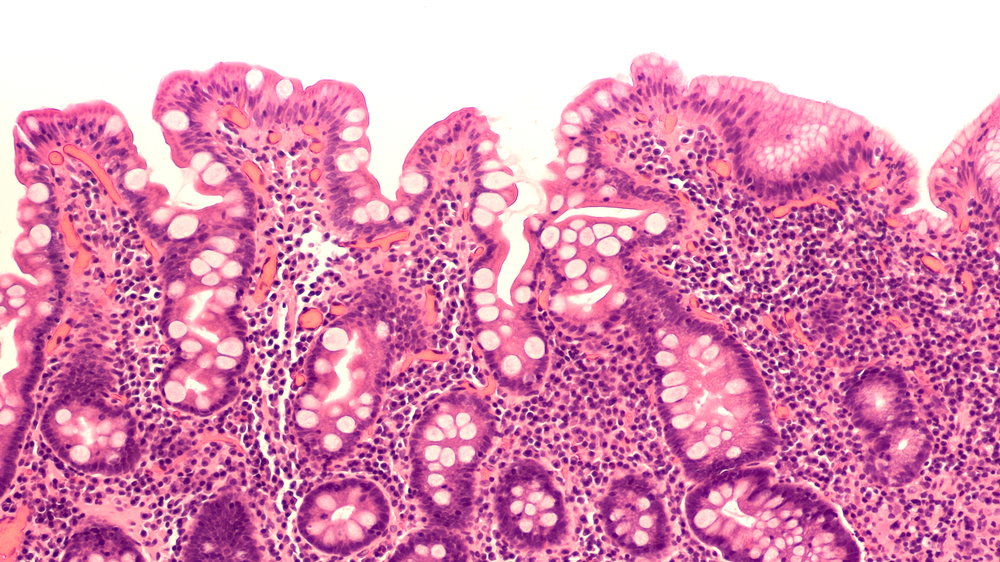

Метаплазия — это замещение нормальных клеток слизистой желудка на клетки, характерные для кишечника. Процесс напоминает «маскировку»: желудок пытается адаптироваться к хроническому воспалению, но такая трансформация повышает риск рака в 6 раз 58.

1. Полная — клетки желудка заменяются на клетки тонкого кишечника. Менее опасна, но требует наблюдения.

2. Неполная — появляются клетки, похожие на эпителий толстой кишки. Именно этот тип чаще перерождается в рак 39.

1. ФГДС с биопсией — «золотой стандарт». Во время процедуры берут образцы ткани для анализа. Современные клиники используют хромоэндоскопию — окрашивание слизистой для точного выявления изменений 10.

3. Гистологическое исследование — подтверждает тип метаплазии и степень риска 36.